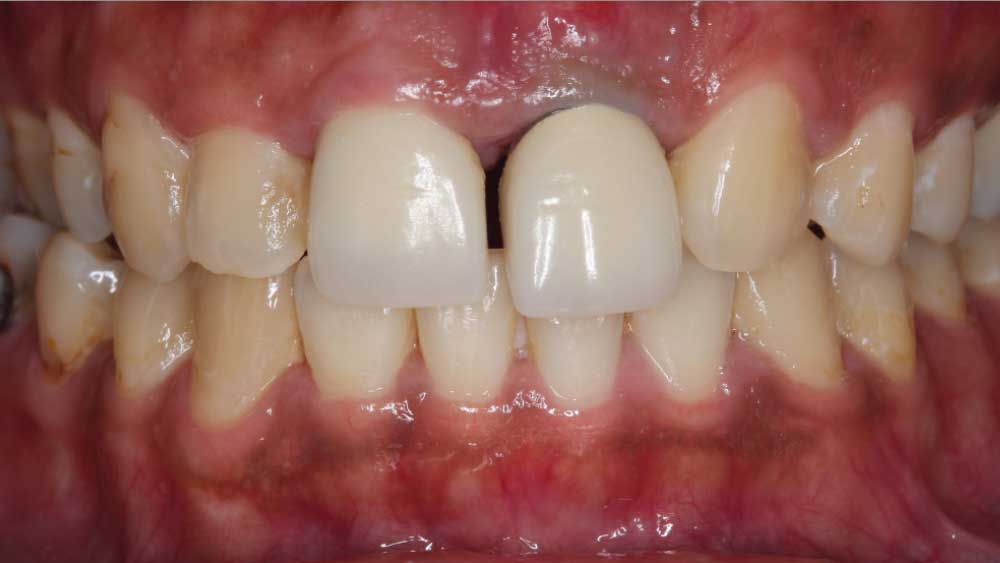

For the first time in many years, Maria is all smiles. It is a dramatic difference from where she was just four months ago. When she arrived in my office, she was so self-conscious I could barely get her to open her mouth. Simple daily tasks like talking and eating had become problematic due to a fractured tooth that was barely attached by an endodontic post. It was so mobile that during our initial visit, Maria was afraid it would fall out while she spoke.

BRIDGING THE GAP WITH BRUXZIR® ESTHETIC

After conducting a thorough diagnostic examination, a vertical root fracture was noted, leaving the #9 central incisor malaligned and unstable. Due to the presence of significant vertical bone loss, extensive treatment for guided bone regeneration and a connective tissue graft would have been required prior to implant placement. After the patient was consulted on these factors, she opted against implant treatment. Once we discussed the remaining options, she decided on a bridge from #8–11 and a veneer on #7. Because she was congenitally missing tooth #10, placing a bridge to restore the edentulous area required preparing the adjacent canine and reshaping it to look like the missing lateral. I selected BruxZir® Esthetic Solid Zirconia as the best material to restore her beautiful smile. Not only does BruxZir Esthetic have superior strength compared to similar all-ceramic materials such as IPS e.max®, but it also has a translucent, natural-looking appearance. Sometimes clinicians think it is risky to do an all-ceramic bridge, but with a strong material like BruxZir Esthetic that has an average flexural strength of 870 MPa, doctors can confidently seat an anterior bridge that will produce long-lasting results. BruxZir has become such a popular material for dentists that it has been utilized to successfully fabricate more than 1.2 million bridges.